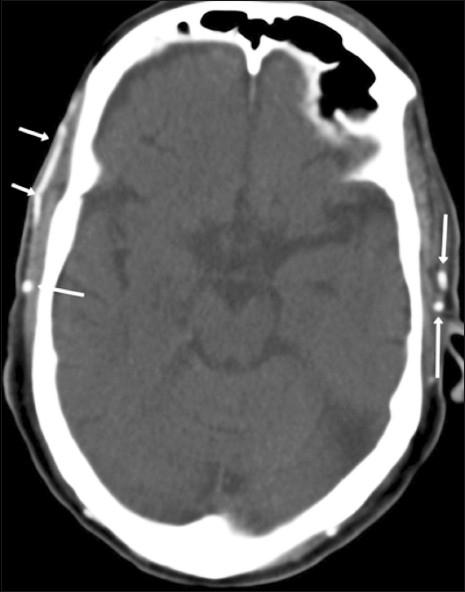

Extracranial superficial temporal artery (STA) calcification is an unusual finding seen in patients with chronic kidney disease and has unknown ramifications with respect to intracranial ischemic disease. We sought to determine the association between the risk factors for vascular calcification and this rare phenomenon, in patients with chronic renal failure, and to assess the coexistence of cerebral ischemia.

Medical records and laboratory data on risk factors for vascular calcification were retrospectively retrieved for 453 patients with a discharge diagnosis of end-stage renal disease (ESRD). CT head examinations were reviewed to identify and associate STA calcification with 1) risk factors for the vascular calcification, 2) intracranial artery calcification, and 3) cerebral ischemia (white matter and/or cortical ischemic changes).

STA calcification was present in 9.9% (45/453) of the studied cohort. The prevalence of cerebral ischemia was 24.4% (11/45) in patients with STA calcification and 9.3% (38/408) in patients without it. Diabetes mellitus (OR: 2.56, 95% CI: 1.059-6.208; P=0.037) was independently associated with the risk of STA calcification. The risk of cerebral ischemia, however, was not related to STA calcification (P=0.221).

The presence of diabetes mellitus is important in describing the risk of STA calcification in patients with ESRD, whereas age, gender, hypertension, serum calcium, serum phosphate, or serum hemoglobin levels are not. The risk of cerebral ischemia is not related to STA calcification but has the strongest association with diabetes mellitus.

颅外颞浅动脉(STA)钙化是慢性肾病患者中一种不常见的表现,其对颅内缺血性疾病的影响尚不清楚。我们试图确定慢性肾衰竭患者血管钙化风险因素与这种罕见现象之间的关联,并评估脑缺血的共存情况。

回顾性检索453例出院诊断为终末期肾病(ESRD)患者的血管钙化风险因素的病历和实验室数据。对头颅CT检查进行评估,以确定STA钙化与以下因素的关联:1)血管钙化的风险因素;2)颅内动脉钙化;3)脑缺血(白质和/或皮质缺血改变)。

在所研究的队列中,9.9%(45/453)的患者存在STA钙化。STA钙化患者的脑缺血患病率为24.4%(11/45),无STA钙化患者的脑缺血患病率为9.3%(38/408)。糖尿病(OR:2.56,95%CI:1.059 - 6.208;P = 0.037)与STA钙化风险独立相关。然而,脑缺血风险与STA钙化无关(P = 0.221)。

糖尿病的存在对于描述ESRD患者STA钙化风险很重要,而年龄、性别、高血压、血清钙、血清磷或血清血红蛋白水平则不然。脑缺血风险与STA钙化无关,但与糖尿病的关联最为密切。